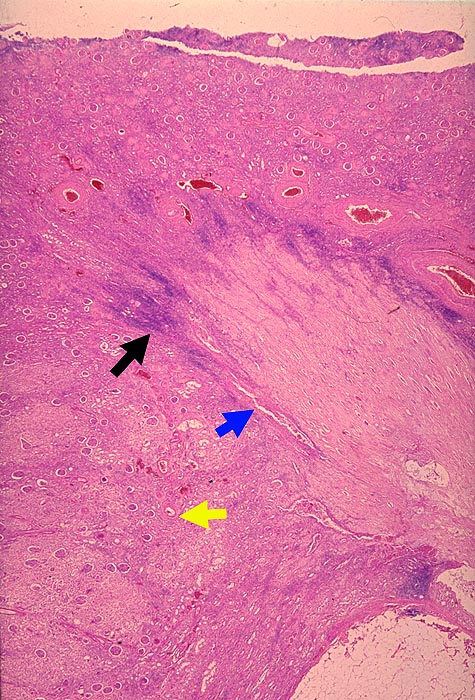

PathoPic – image database / PathoPic ID 1633 - Papillennekrosen bei Analgetikanephropathie

Papillennekrosen bei Analgetikanephropathie

Papille und grösster Teil des Nierenmarks sind vollständig nekrotisch. Die Papillennekrose wird mantelartig von einem überwiegend lymphozytären Infiltrat umgeben. In der Randzone der Papillennekrose typische schlitzförmige Defekte (die z.T. röntgenologisch dargestellt werden können). Die Nierenrinde über der Papillennekrose ist geschrumpft und eingesunken. Das Nierengewebe im Bereich der Columna Bertini ist wesentlich besser erhalten als das Rindengewebe unmittelbar über der Papillennekrose.